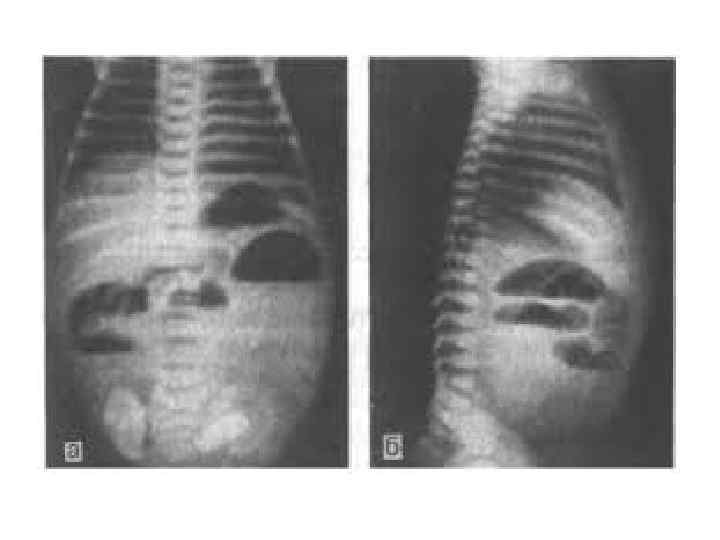

• Рентгенография брюшной полости: определение газа и уровней жидкости в петлях кишок (чаши Клойбера) поперечная исчерченность кишки (симптом керкринговых складок) • УЗИ: • при механической кишечной непроходимости: расширение просвета кишки более 2 см с наличием феномена «секвестрации жидкости» в просвет кишки; утолщение стенки тонкой кишки более 4 мм; наличие возвратно поступательных движений химуса по кишке; увеличение высоты керкринговых складок более 5 мм; увеличение расстояния между керкринговыми складками более 5 мм; гиперпневматизация кишечника в приводящем отделе • при динамической кишечной непроходимости: отсутствие возвратно поступательных движений химуса по кишке; феномен секвестрации жидкости в просвет кишки; невыраженный рельеф керкринговых складок; гиперпневматизация кишечника во всех отделах